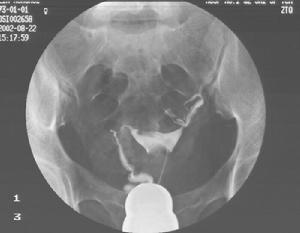

輸卵管先天性畸形不易被發現,原因首先是常與生殖道先天畸形同時存在而被忽略,其二是深藏在盆腔側方。常用的診斷方法,子宮輸卵管造影術後發現單角子宮單側輸卵管或雙輸卵管。腹腔檢查可能發現各種畸形。剖腹術可較明確的診斷。